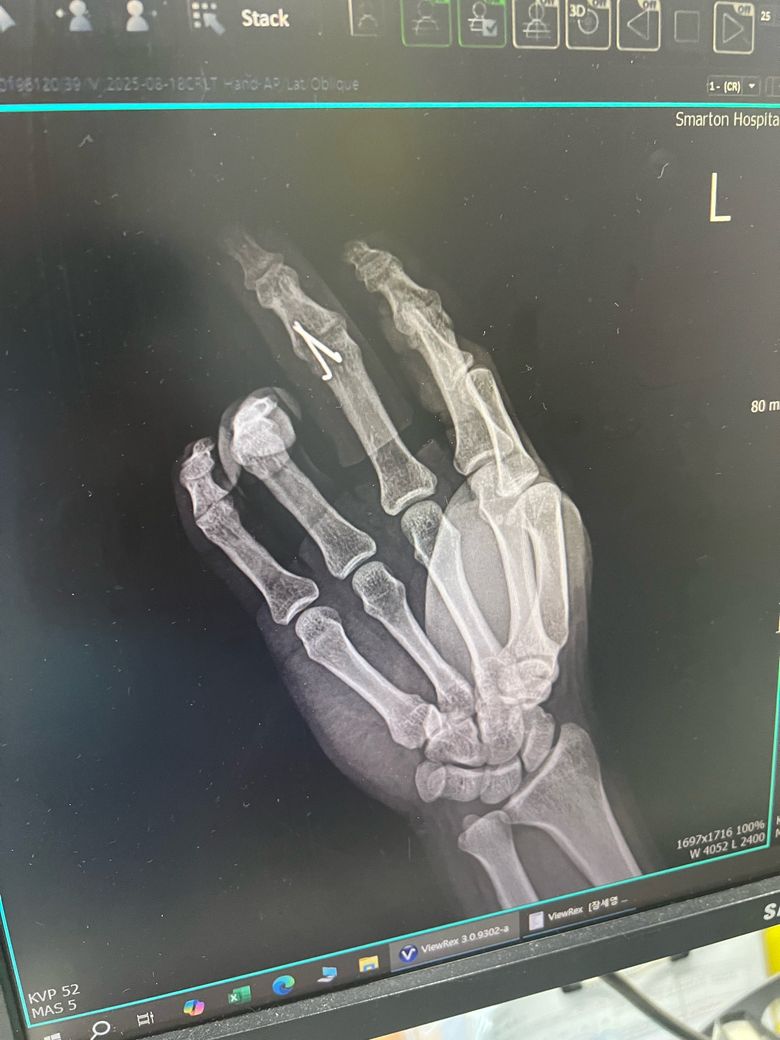

손가락 마디 골절로(미세) 핀박는 수술했어요

8월 18일에 수술하였고 이틀에 한번씩 오라고해서 맨날 가서 드레싱하고 있는데요. 술 담배 일절 끊고 치료에만 전념중인데 의사선생님께서 6주는 지나고 뽑자는데 솔직히 6주는 너무 길다고 생각되서요.

3.골절상태 엑스레이 보시면 몇주정도 후에 핀 뽑아도 되는지 판단부탁드립니다.

• 1번 째 사진

• 2번 째 사진

• 3번 째 사진

3. 올리신 사진만으로 구체적인 판단을 내리기에는 근거가 충분하지 않습니다만, 손가락 부위 골절이라면 4주 만에 핀을 뽑는 경우도 있긴 하겠습니다. 그보다 자세히 어떻다고 이야기를 드리기는 조심스럽습니다.